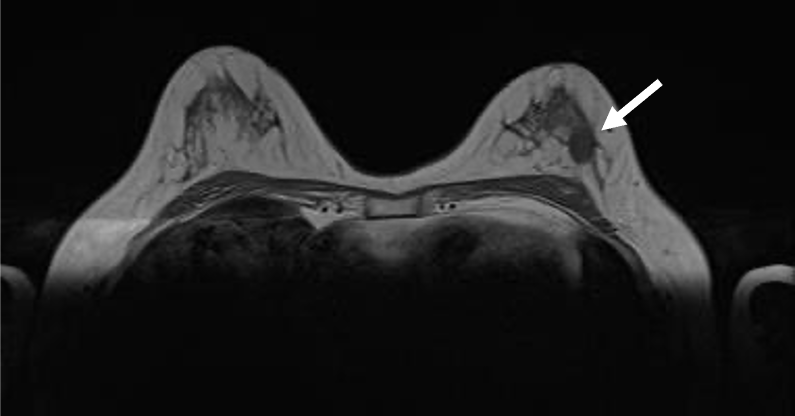

検診で指摘された左乳房腫瘤に対してMRI精査を行った症例である。BPEはminimalで病変の同定は容易であった。拡散強調像では明瞭な高信号あり、ADCの低下を認め、細胞密度は高いと考えられた。造影MRIにて辺縁不整な形状である事が明瞭となり、ダイナミック早期相では辺縁優位に造影効果を認め、TIC( Time intensity curve)ではFast-plateauパターンを示し乳癌を疑った。

cT1cN0M0の診断となり乳房温存術、術後放射線療法が施行された。

病理では硬性型の浸潤性乳管癌と診断された。

当該疾患の診断における造影MRIの役割

病変の辺縁の性状、境界、内部の造影パターンの把握にダイナミック造影MRIが必須である。今回の症例は単発病変であったが、多発病変でBPE(background parenchymal enhancement)がある症例では病変部と非病変部の区別に注意が必要である。